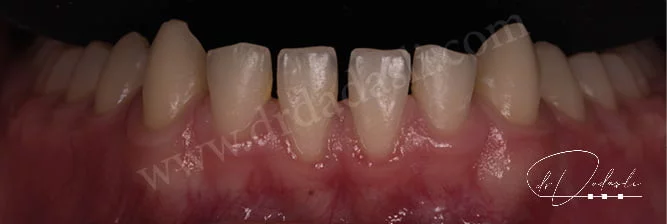

- Ters kapanış (Şekil 2 ve Şekil 3) – bu durumda alt ön dişler üst ön dişlerin gerisinde bulunmaları gerekirken önünde konumlanmıştır. Bu durumun ortodonti bilimindeki ismi Sınıf III maloklüzyondur.